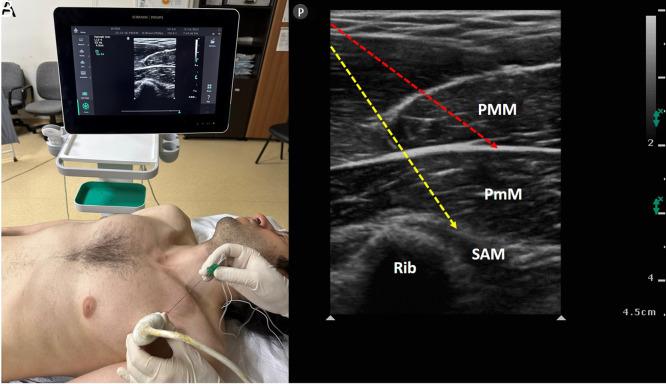

Regional anesthesia has benefits beyond just treating acute postoperative pain. Interfascial plane blocks, which have been very popular with ultrasound in recent years, function primarily by administering a high volume of a local anesthetic to the fascial plane. Contrary to traditional peripheral nerve blocks, the targeted nerve or structure in interfacial plane blocks is not fully defined, and the indications have not been fully revealed yet. Anatomical, cadaveric, and radiological studies show how effective the interfascial plane blocks play a role. This review focuses on the benefits, techniques, indications, and complications of interfascial plane blocks in the context of breast, thoracic, and orthopedic surgery.

区域麻醉的益处不仅仅局限于治疗术后急性疼痛。近年来,筋膜平面阻滞在超声引导下非常流行,其主要作用机制是在筋膜平面注射大量局部麻醉药。与传统的外周神经阻滞不同,筋膜平面阻滞中所针对的神经或结构尚未完全明确,其适应证也尚未完全揭示。解剖学、尸体研究和影像学研究表明了筋膜平面阻滞发挥作用的有效性。本综述重点关注在乳腺、胸科和骨科手术背景下筋膜平面阻滞的益处、技术、适应证及并发症。